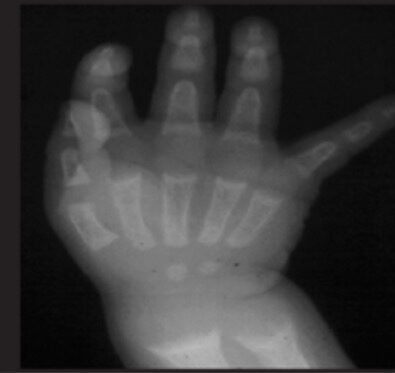

Wrist X-ray of a child with rickets shows metaphyseal cupping.

Image: “Radiological appearance” by Atatürk University, Faculty of Medicine, Department of Pediatric Endocrinology, Erzurum, Turkey. License: CC BY 2.5